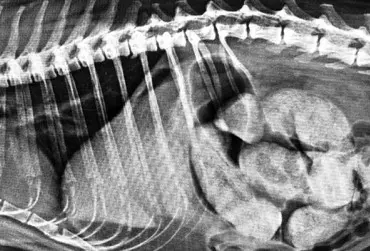

Określenie „rozpoznanie cioci Minnie” pochodzi ze Stanów Zjednoczonych i jest żartobliwym określeniem rozpoznania patognomonicznego, stosowanym głównie przez radiologów. Zwrot ten stał się popularny w latach 90. XX w. za sprawą strony internetowej o takim tytule. Obecnie to określenie stosuje się również w metodologii nauczania klinicznego. W artykule przedstawiono przypadki rozpoznań „cioci Minnie” z własnego archiwum ultrasonografii jamy brzusznej małych zwierząt.